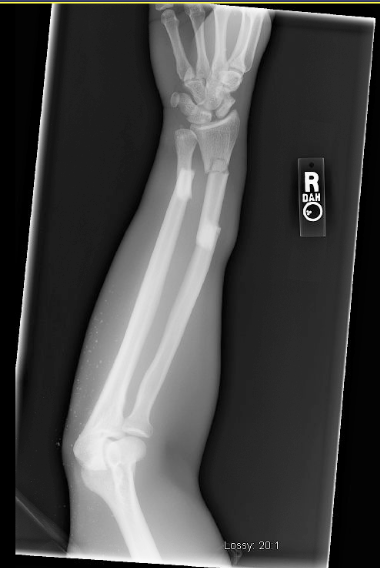

![]() |

| Grashey view shows the height of the prosthesis and alignment |